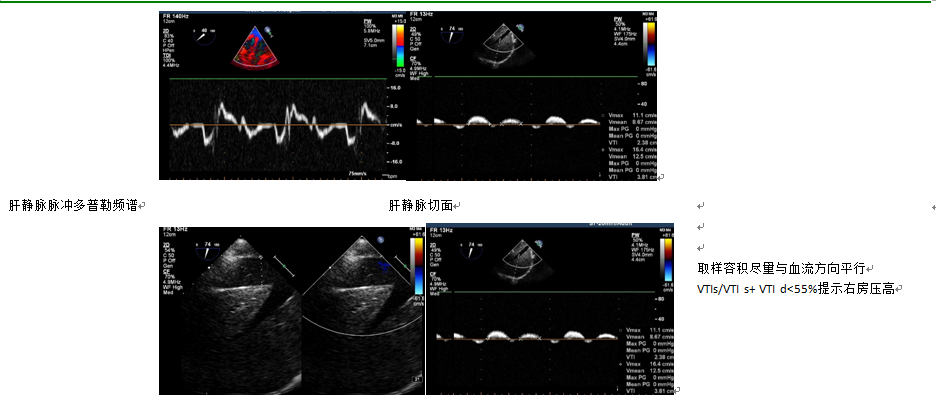

TEE可有效评估左心室舒张功能,常用指标包括:左心房舒张末容积指数、二尖瓣口前向血流、肺静脉血流和二尖瓣侧壁或间壁组织多普勒频谱等。二尖瓣环侧壁瓣环峰≤10cm/s和跨二尖瓣的E/≤8cm/s可提示左室舒张功能障碍。左室舒张功能障碍分为4期:正常、松弛障碍、假性正常、限制性充盈。随病情进展,各期二尖瓣前向血流、二尖瓣环组织多普勒、肺静脉血流频谱和二尖瓣彩色M型血流传播速度等指标的演变见图9。左室舒张功能障碍可引起左房压力的改变,多种指标可评估左房压力,其评估流程见图10。

什么叫超声容积探头围手术期经食管超声心动图监测操作的专家共识(可下载)_https://www.jmylbn.com_新闻资讯_第51张

图9 超声多普勒评价左室舒张功能分期